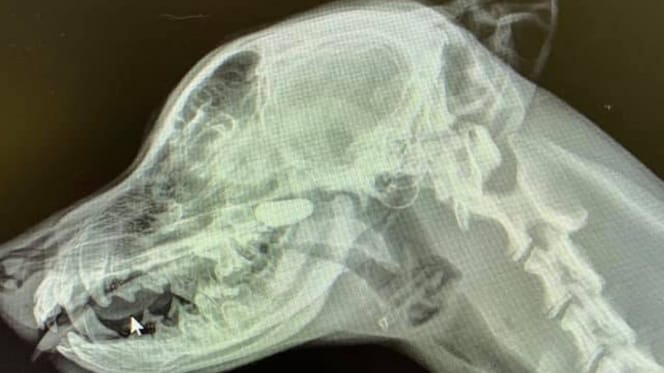

Radiographie de la tête d'un chien

© Sarah Yuki @Iloveveterinarymedicine / Facebook

La vétérinaire poursuit donc ses recherches et demande de faire des radiographies du jeune chien. D'abord le thorax, mais Sarah a beau regarder, elle ne voit rien de suspect sur le cliché. Elle demande alors une radio de profil de la tête et du cou. Et cette fois, c'est la bonne !

Dans les cavités nasales, on distingue clairement un corps étranger qui n'a absolument rien à faire là. Il s'agit en fait d'un caillou que le chiot a réussi à s'introduire dans le nez. Une fois l'objet retiré, le petit labrador s'est tout de suite senti beaucoup mieux.